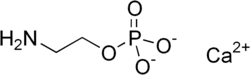

Calcium 2-aminoethylphosphate

Calcium 2-aminoethylphosphate (Ca-AEP or Ca-2AEP) is a compound discovered by the biochemist Erwin Chargaff in 1941. It is the calcium salt of phosphorylethanolamine. It was patented by Hans Alfred Nieper and Franz Kohler.

Calcium 2-amino ethyl phosphoric acid (Ca-AEP or Ca-2AEP) is also called calcium ethylamino-phosphate (calcium EAP), calcium colamine phosphate, calcium 2-aminoethyl ester of phosphoric acid, and calcium 2-amino ethanol phosphate

2-AEP plays a role as a component in the cell membrane and at the same time has the property to form complexes with minerals. This mineral transporter goes into the outer layer of the outer cell membrane where it releases its associated mineral and is itself metabolized with the structure of the cell membrane.